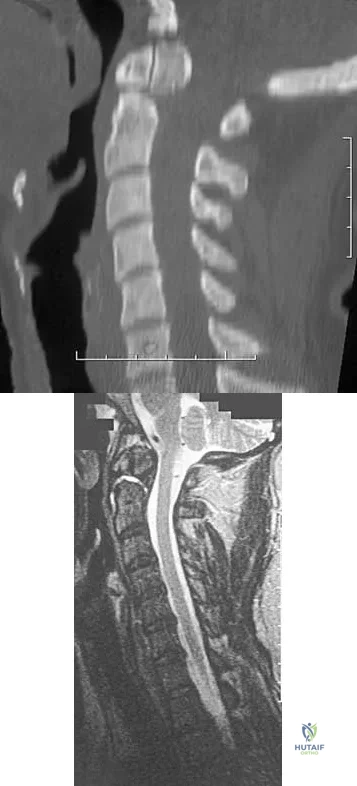

A 42-year-old woman reports that she has low back pain and had a transient loss of consciousness after falling off a horse. She denies having neck pain but notes that she was involved in a motor vehicle accident 2 years ago and had neck pain at that time. Examination reveals full range of motion of the neck and no localized tenderness. The neurologic examination is normal. A lateral radiograph of the cervical spine is obtained. Figures 41a and 41b show CT and MRI scans. What is the most likely diagnosis?

Explanation